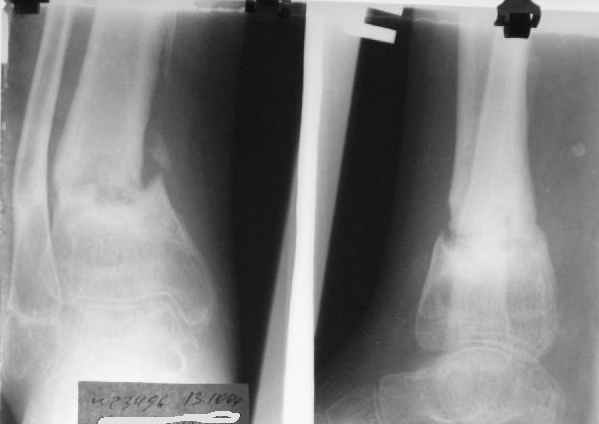

Ребенок 12 лет, поступил после падения с высоты примерно 2,5м.

Перелом костей н\3 правой голени со смещением. Перелом большеберцовой кости можно охарактеризовать как компрессионно-оскольчатый.

Скелетное вытяжение за пяточную кость.

В первые сутки значительный отек с\3, н\3голени, стопы с развитием практически неуловимого в нашей стране ;) компартмент синдрома (фасциотомии не проводилось), недочеты по укладке на скелетном

вытяжении.

Формирование некроза кожи по задней поверхности н\3 голени~ 1 %, вторичное заживление, кожная пластика. Нейропатия м\берцового нерва (отсутствие активного разгибания 1 пальца) На вытяжении около 8 нед, в дальнейшем в гипсовых повязках ~ 8 мес.